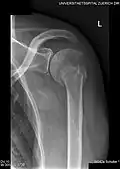

X-ray at left shows anterior dislocation in a young man after trying to get up from his bed. X-ray at right shows same shoulder after reduction and internal rotation, revealing both a bony Bankart lesion and a Hill-Sachs lesion. -

Radiograph showing a bony Bankart lesion with stationary fragment at the inferior glenoid -